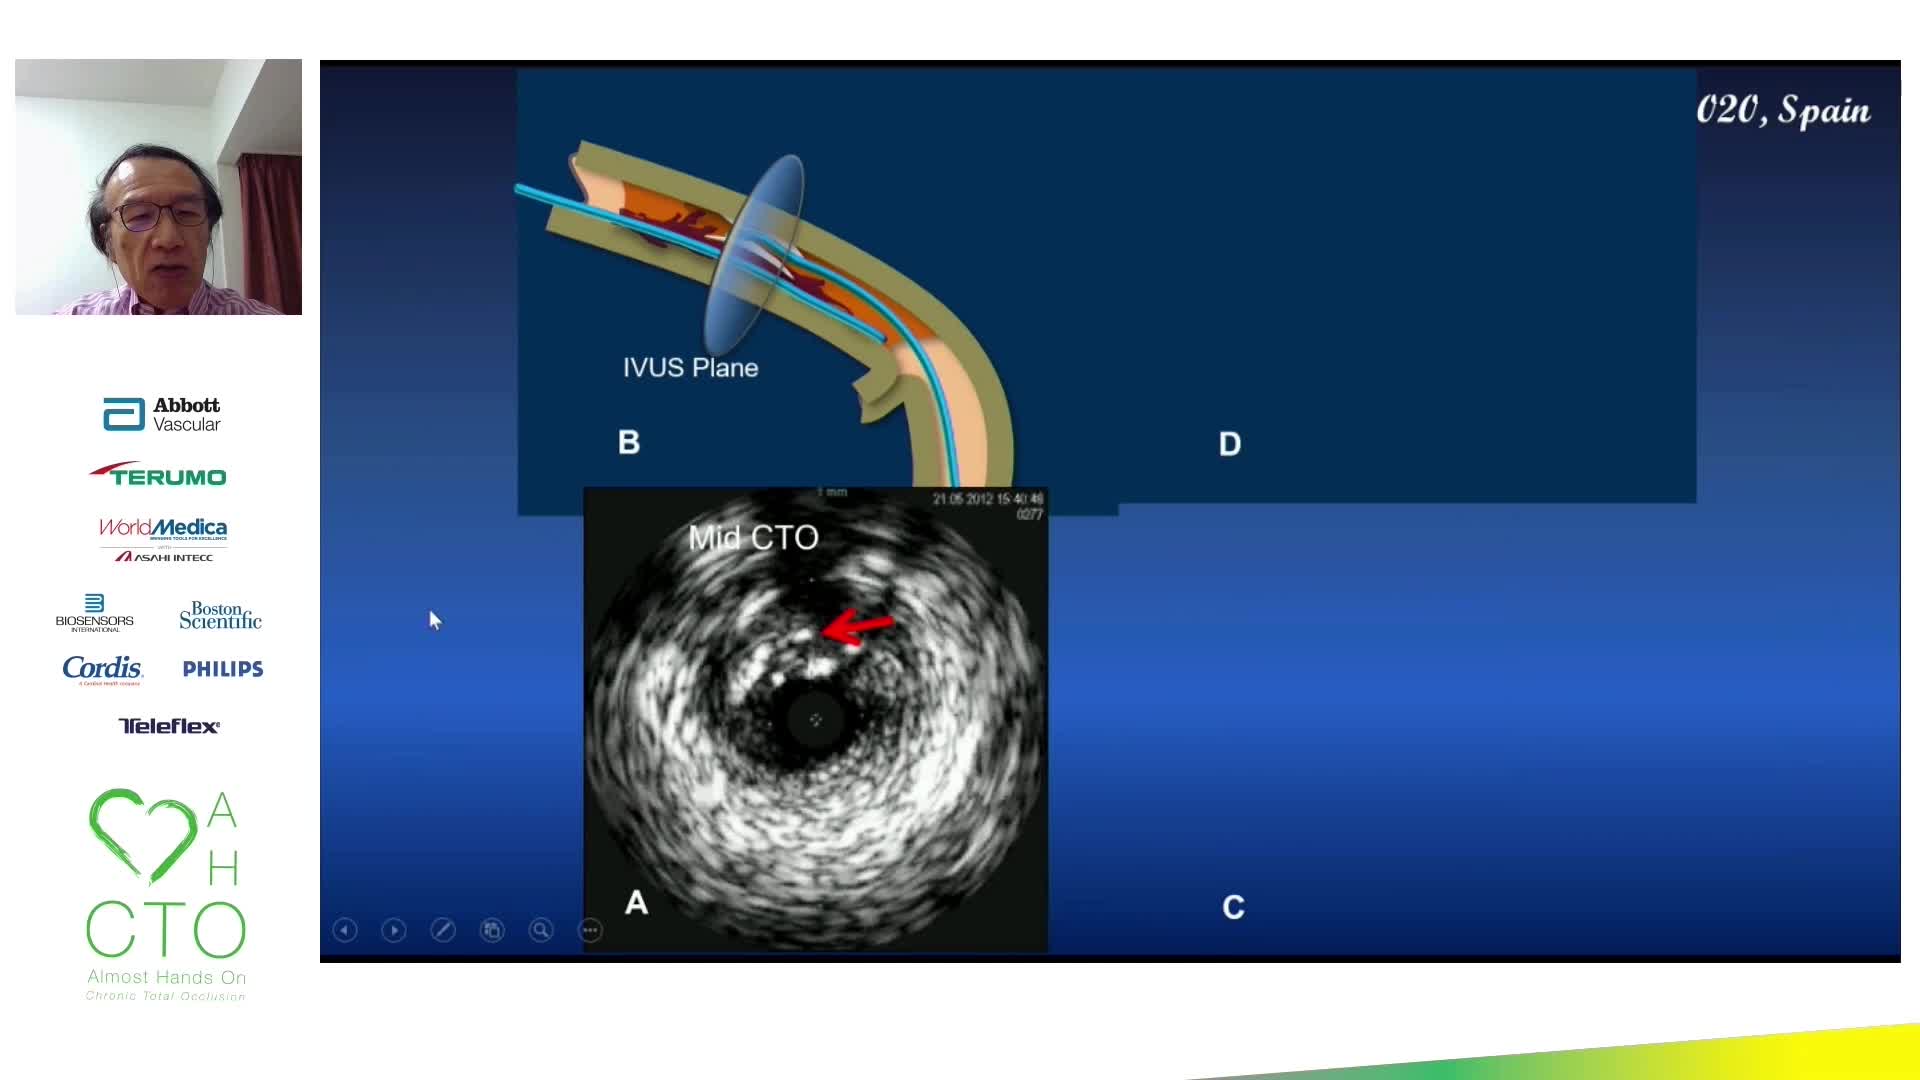

• Chronic Total Occlusion (CTO)

• Intravascular Ultrasound (IVUS)

Retrograde case